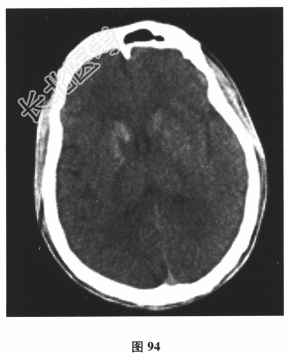

患者男,24岁。由于“反复发作性四肢抽搐3个月,言语困难1d”到院就诊。3个月前饮酒后出现四肢抽搐、意识丧失,持续3min左右自行缓解;10d前再发一次四肢抽搐。遂行颅脑CT(图94)及MRI平扫检查(图95)后予丙戊酸钠对症治疗。1d前再发四肢抽搐,出现言语困难。其母亲有糖尿病病史。查体:身材矮小,意识清楚,感觉性失语,四肢肌力、肌张力正常,腱反射对称活跃,深、浅感觉正常,病理反射未引出,脑膜刺激征(-)。脑脊液:压力110mmH₂O,细胞、蛋白、葡萄糖、氯化物均正常,乳酸3.6mmol/L↑。